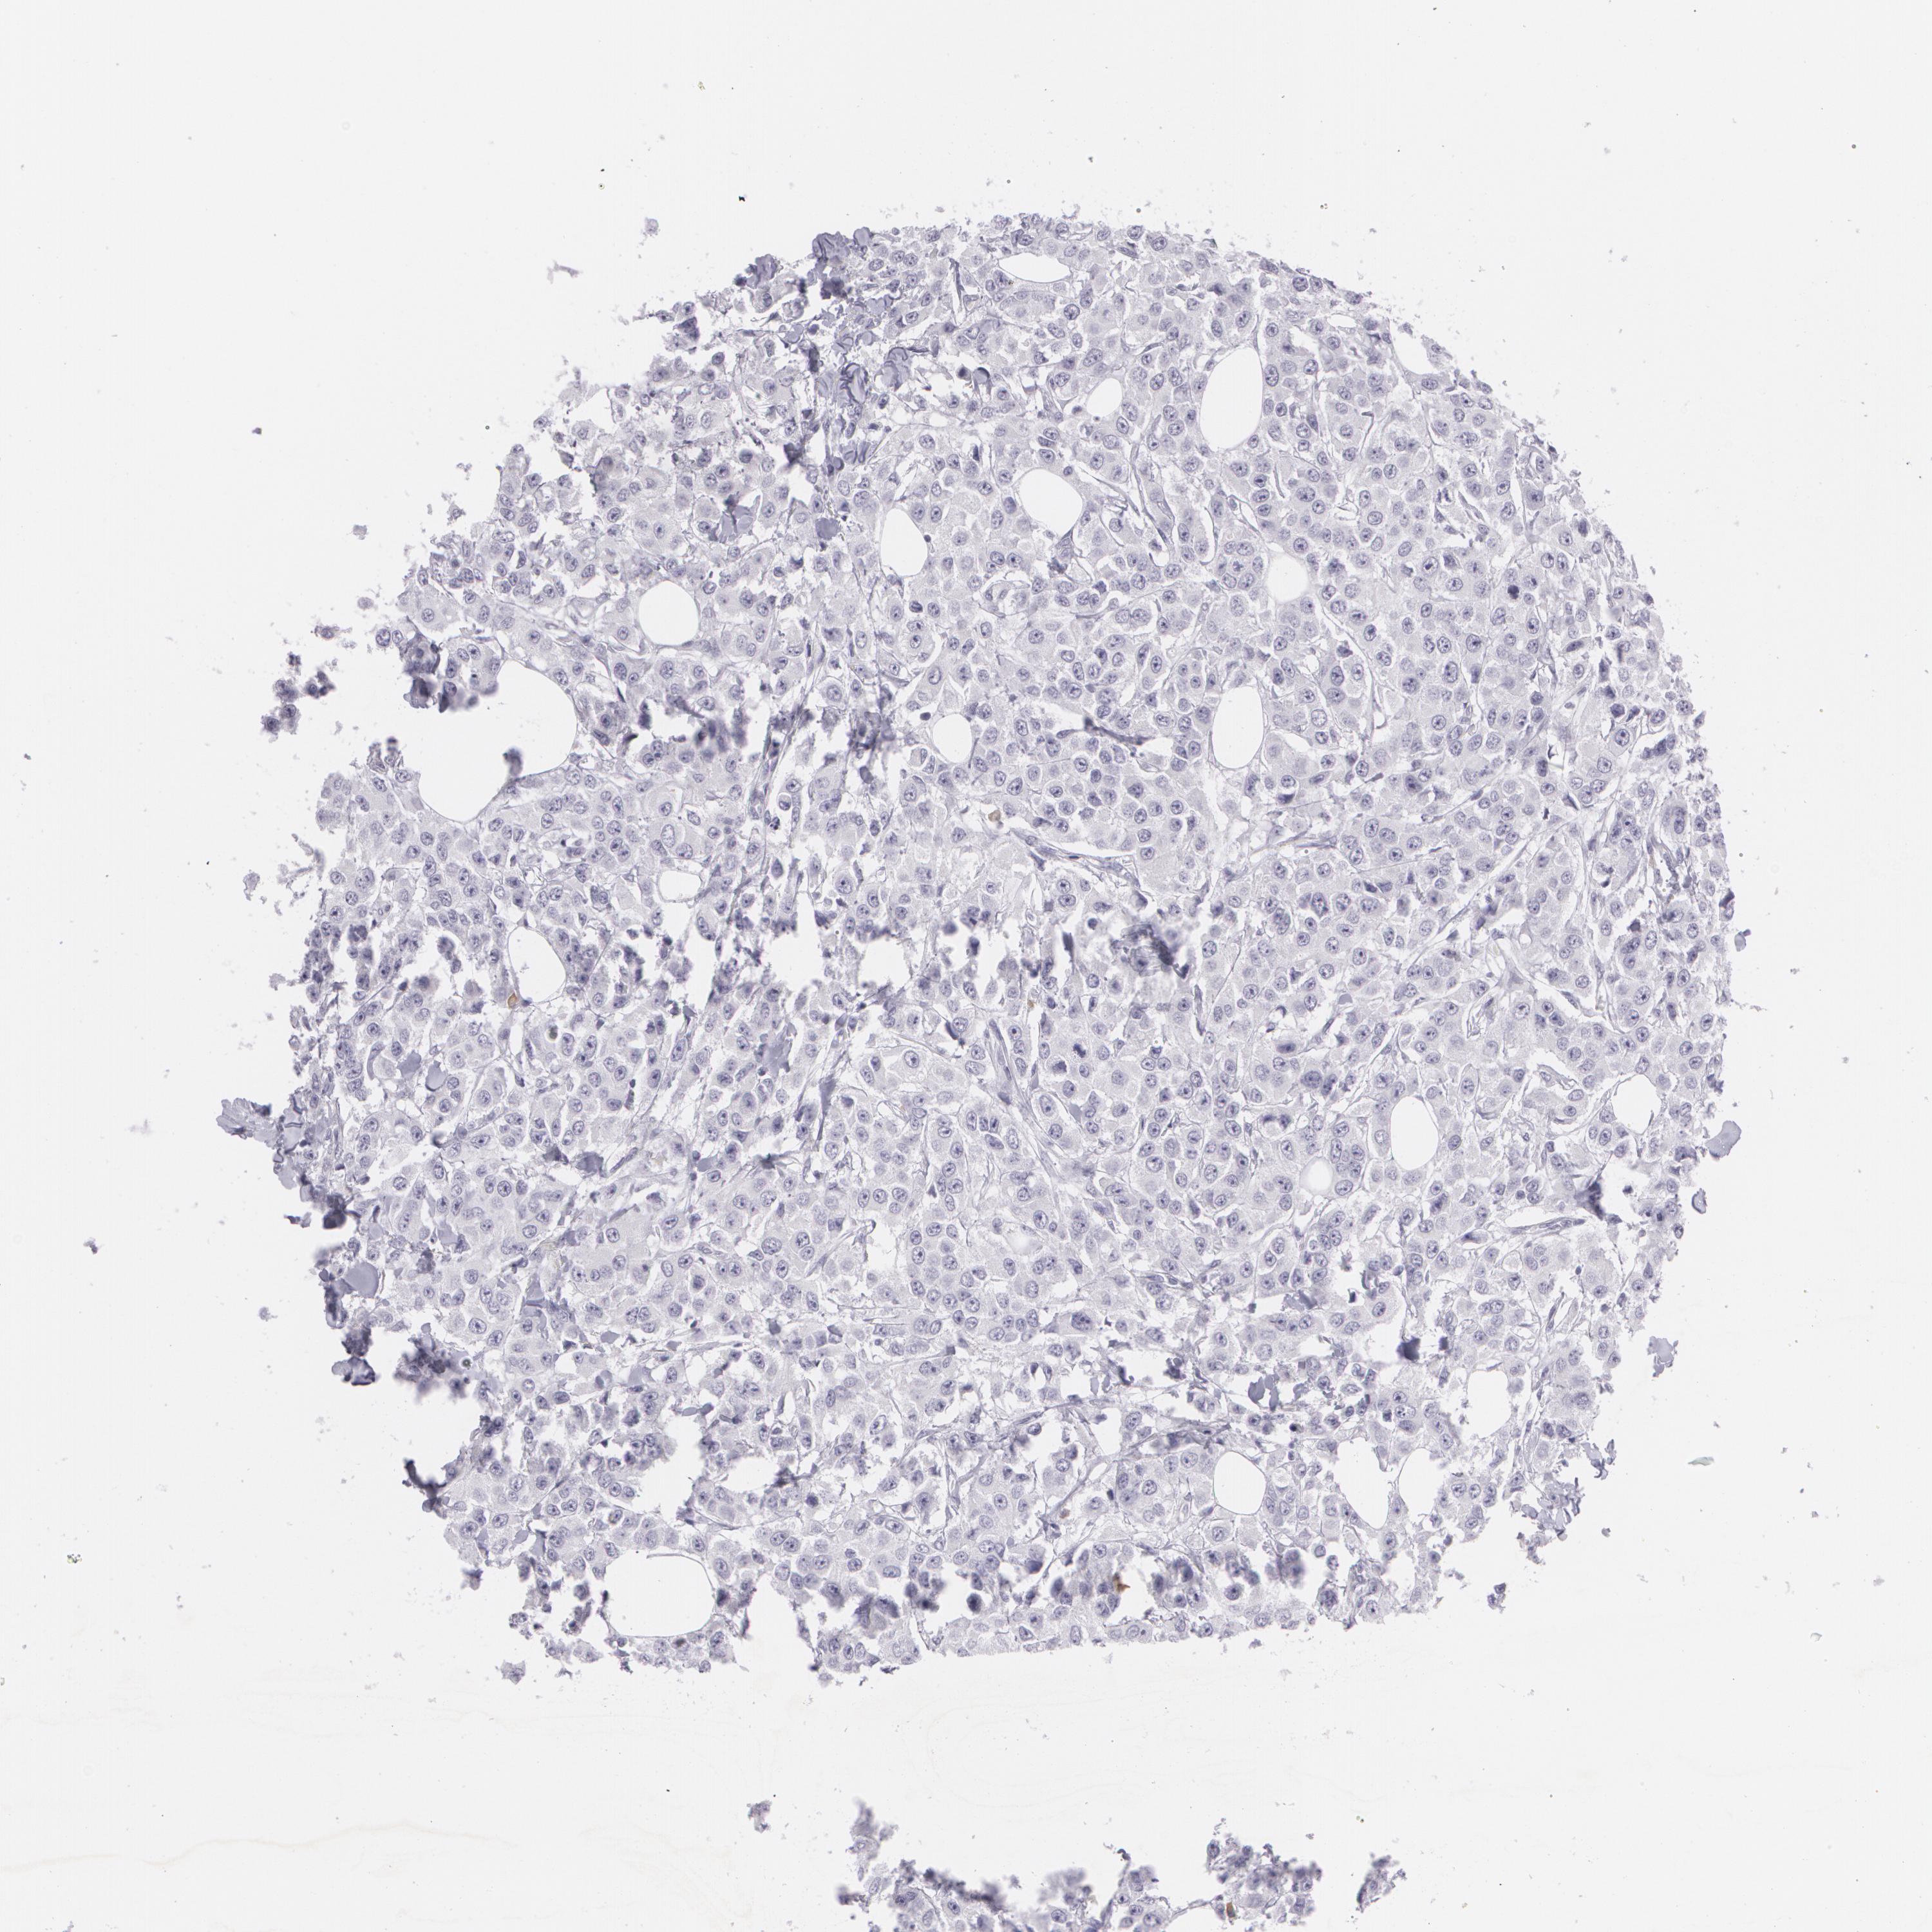

CANCER BREAST CANCER Show tissue menu

Breast cancer

Human cancer